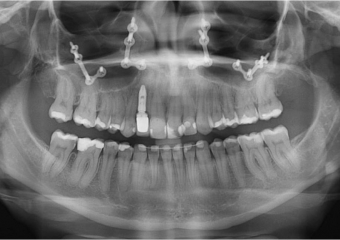

Raio X inicial - Clínica Cliniface

Raio X inicial